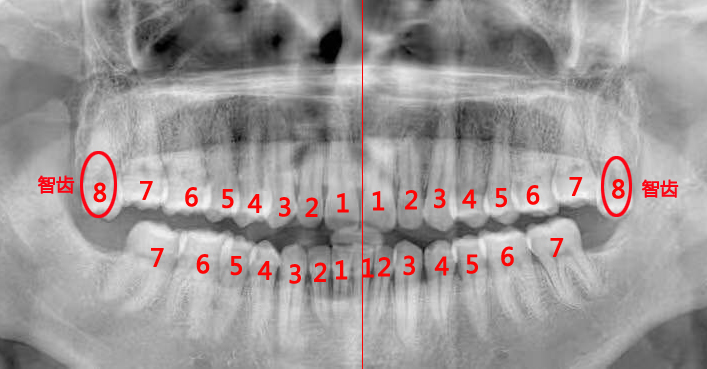

最简单的方法:对着镜子,从一侧的门牙开始往后数,第8颗就是智齿。

最准确的方法:拍片检查,借助X光让智齿现形。

说明:检查智齿或拔智齿前,医生一般都会建议拍个全景片,很多人觉得麻烦,其实这是非常有必要的。全景片可以清晰地呈现上下颌骨、全口牙列的全貌,以及智齿与邻牙、周围牙槽骨的关系,帮助医生评估拔牙的难度,并安全快速地拔除智齿。拍片时,需要穿防护服。